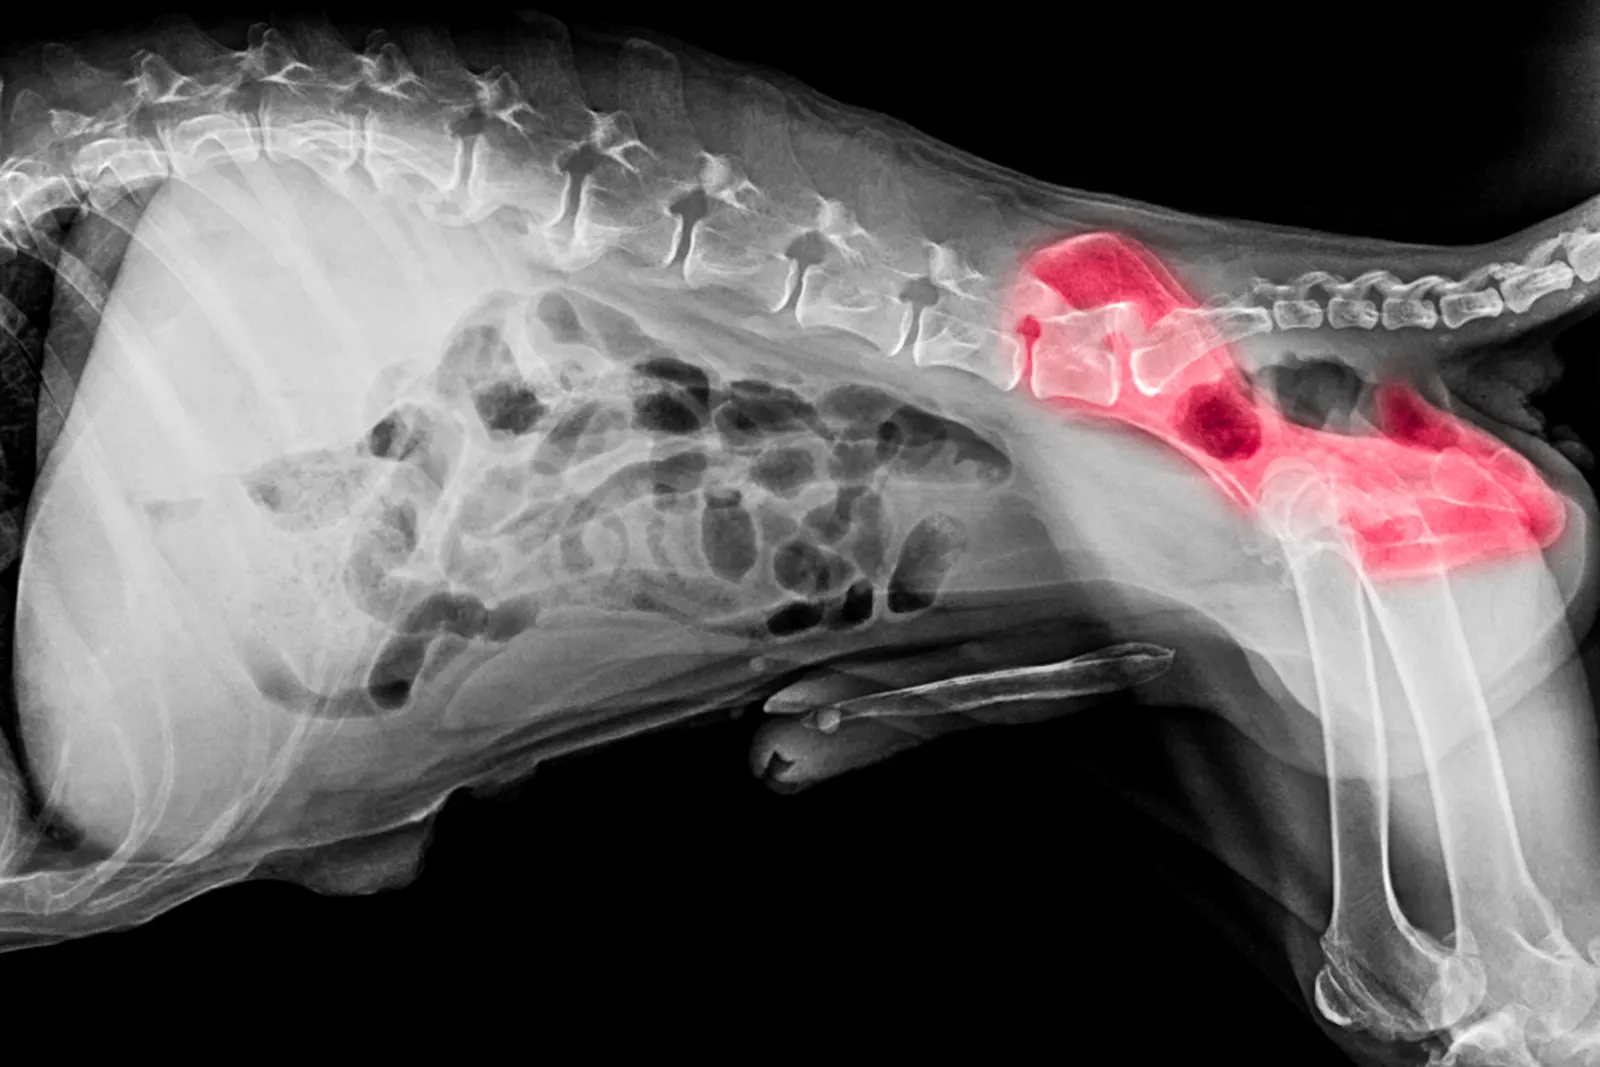

Osteochondrosis dissecans je razvojna bolest koja se ponekad pojavljuje u brzorastućih pasa, kada brzi razvoj hrskavice može nadmašiti vlastitu opskrbu krvlju, uzrokujući abnormalni razvoj hrskavice koji rezultira šepanjem, boli i posljedičnim osteoartritisom.

U nekim slučajevima dolazi do odvajanja promijenjenih dijelova hrskavice od preostalog dijela površine hrskavice.

Genetski čimbenici najvažniji su uzročnici OKP-a, posebice pasminska predispozicija, najčešće kod divovskih pasmina.

Dijeta ili prehrambena ograničenja u prvih nekoliko mjeseci života, hormonska neravnoteža ili trauma zglobova također povećavaju rizik od OKP-a.

Većina pasa s OKP-om pokazuje kliničke simptome prije prve godine starosti, iako se ponekad, osobito kada je riječ o OKP-u ramena, klinički znakovi mogu pojaviti i kod starijih pasa. Klinički znakovi su varijabilni i ovise o vrsti zahvaćenog zgloba i veličini defekta hrskavice.

Najčešći klinički znakovi su šepanje, ukočenost, otok i bol u zglobu, smanjena aktivnost ili općenito "depresivno" ponašanje.

Prvi u nizu je ortopedski pregled, a zatim RTG snimanja suspektnih zglobova iz više projekcija, obično u sedaciji.

OCD se može pojaviti istovremeno s drugim razvojnim bolestima (npr. displazija lakta) i tada pacijentu mogu biti potrebne napredne dijagnostičke metode (CT, MRI).

Kako se OCD počinje razvijati u određenom zglobu; tada se na tom zglobu počinje razvijati osteoartritis (upala zgloba).

Kada se osteoartritis jednom počne razvijati, ne može se izliječiti, ali se kod većine pacijenata može uspješno kontrolirati.